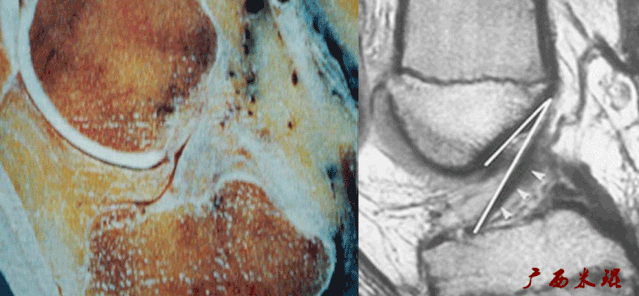

6)假瘤:

-

韧带损伤后断端较整齐,残端组织增生并被滑膜包裹呈“瘤状”,如果突出于前方为“独眼征”。

多见于韧带股骨附着部撕裂及部分撕裂。